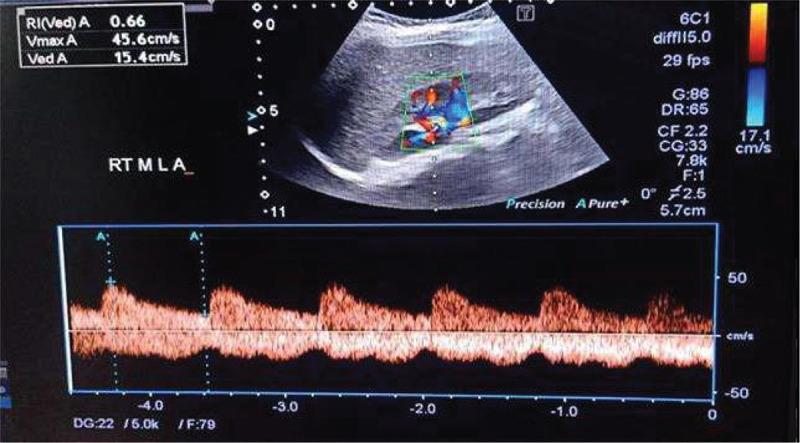

The present case-control study was conducted on 60 children with INS and 60 age- and sex-matched healthy children. All participants were subjected to evaluation of serum levels of IL-13 and An-V and ultrasound Doppler measurement of CIMT and renal RI.

本病例对照研究对60例INS患儿和60例年龄及性别匹配的健康儿童进行。所有参与者均接受IL - 13和An - V血清水平评估以及CIMT和肾RI的超声多普勒测量。

与健康对照相比,患者的An - V水平(5.9±2.6 vs. 2.1±0.8 ng/mL,p<0.001)和IL - 13水平(19.2±7.6 vs. 3.4±1.4 ng/L)显著更高。此外,与对照组相比,患者的CIMT也显著更高(0.49±0.06 vs. 0.35±0.03,p<0.001)。研究组之间在右侧或左侧RI方面未发现显著差异。相关性分析确定血清An - V水平与白蛋白/肌酐比值(ACR)(r = 0.55)、胆固醇(r = 0.48)、甘油三酯(r = 0.36)、IL - 13(r = 0.92)和CIMT(r = 0.53)之间存在显著正相关。血清IL - 13水平与CIMT测量值及相应参数之间也存在类似的相关性。